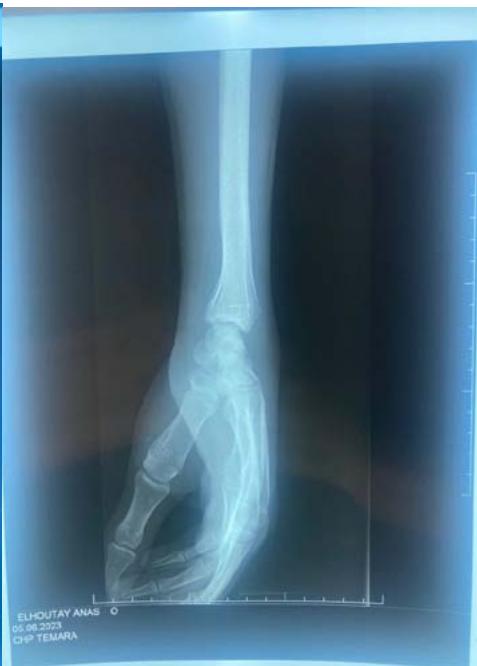

The standard radiographic assessment revealed a scaphoid fracture with an underlying gap, suggesting the possibility of a cyst or pseudarthrosis of the scaphoid (figure 1). The wrist CT scan confirmed the scaphoid fracture with a probable intraosseous cyst (figure 2).

Figure 2: The computed tomography (CT) scan confirmed the scaphoid fracture and the localized and nonaggressive nature of the cyst.